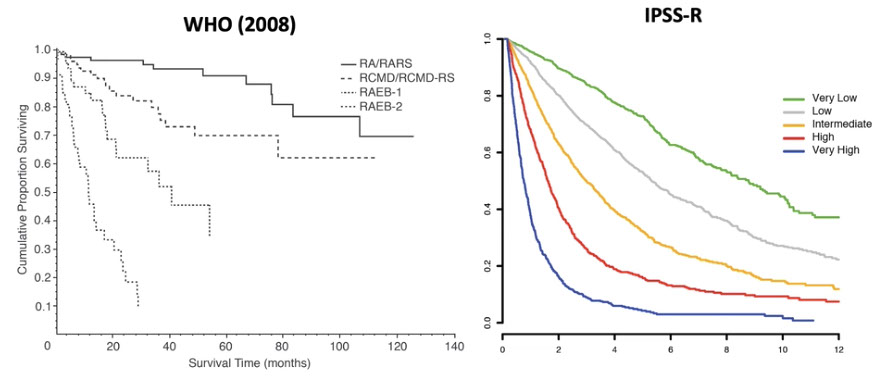

Intl. Prognostic Scoring System (IPSS) categorizes % blasts, karyotype, and # cell lines c cytopenia and gives px

MDS diagnosis and IPSS-R [3]

MDS risk stratification: both IPSS-R and WHO provide complimentary and clinically relevant data. Malcovati L et al. J Clin Oncol 2005; 237594, Greenburg et al Blood 2012; 120:2454; clinicians may tello pts both WHO category and IPSS risk score